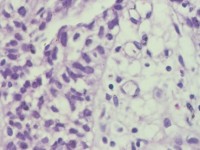

咔血3月,纤维支气管镜:右侧肺下叶基底段黏膜增生。能诊断肺部鳞状细胞癌吗?

建议:CK5/6;P63等,排除鳞癌。

鳞癌。